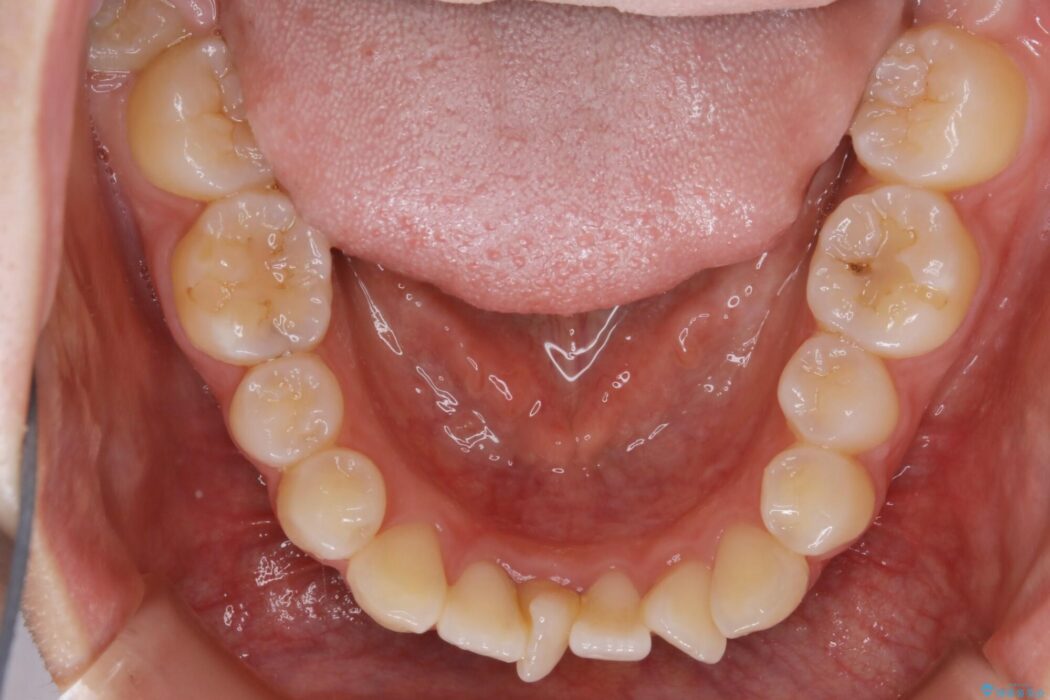

上下前歯のねじれなどで生じている歯列のガタつきをなおしたいとのことで来院されました。

特に前歯部分に90度近く捻転した歯、斜めに生えている歯などによる歯列のがたつき、正中のズレが目立っていました。